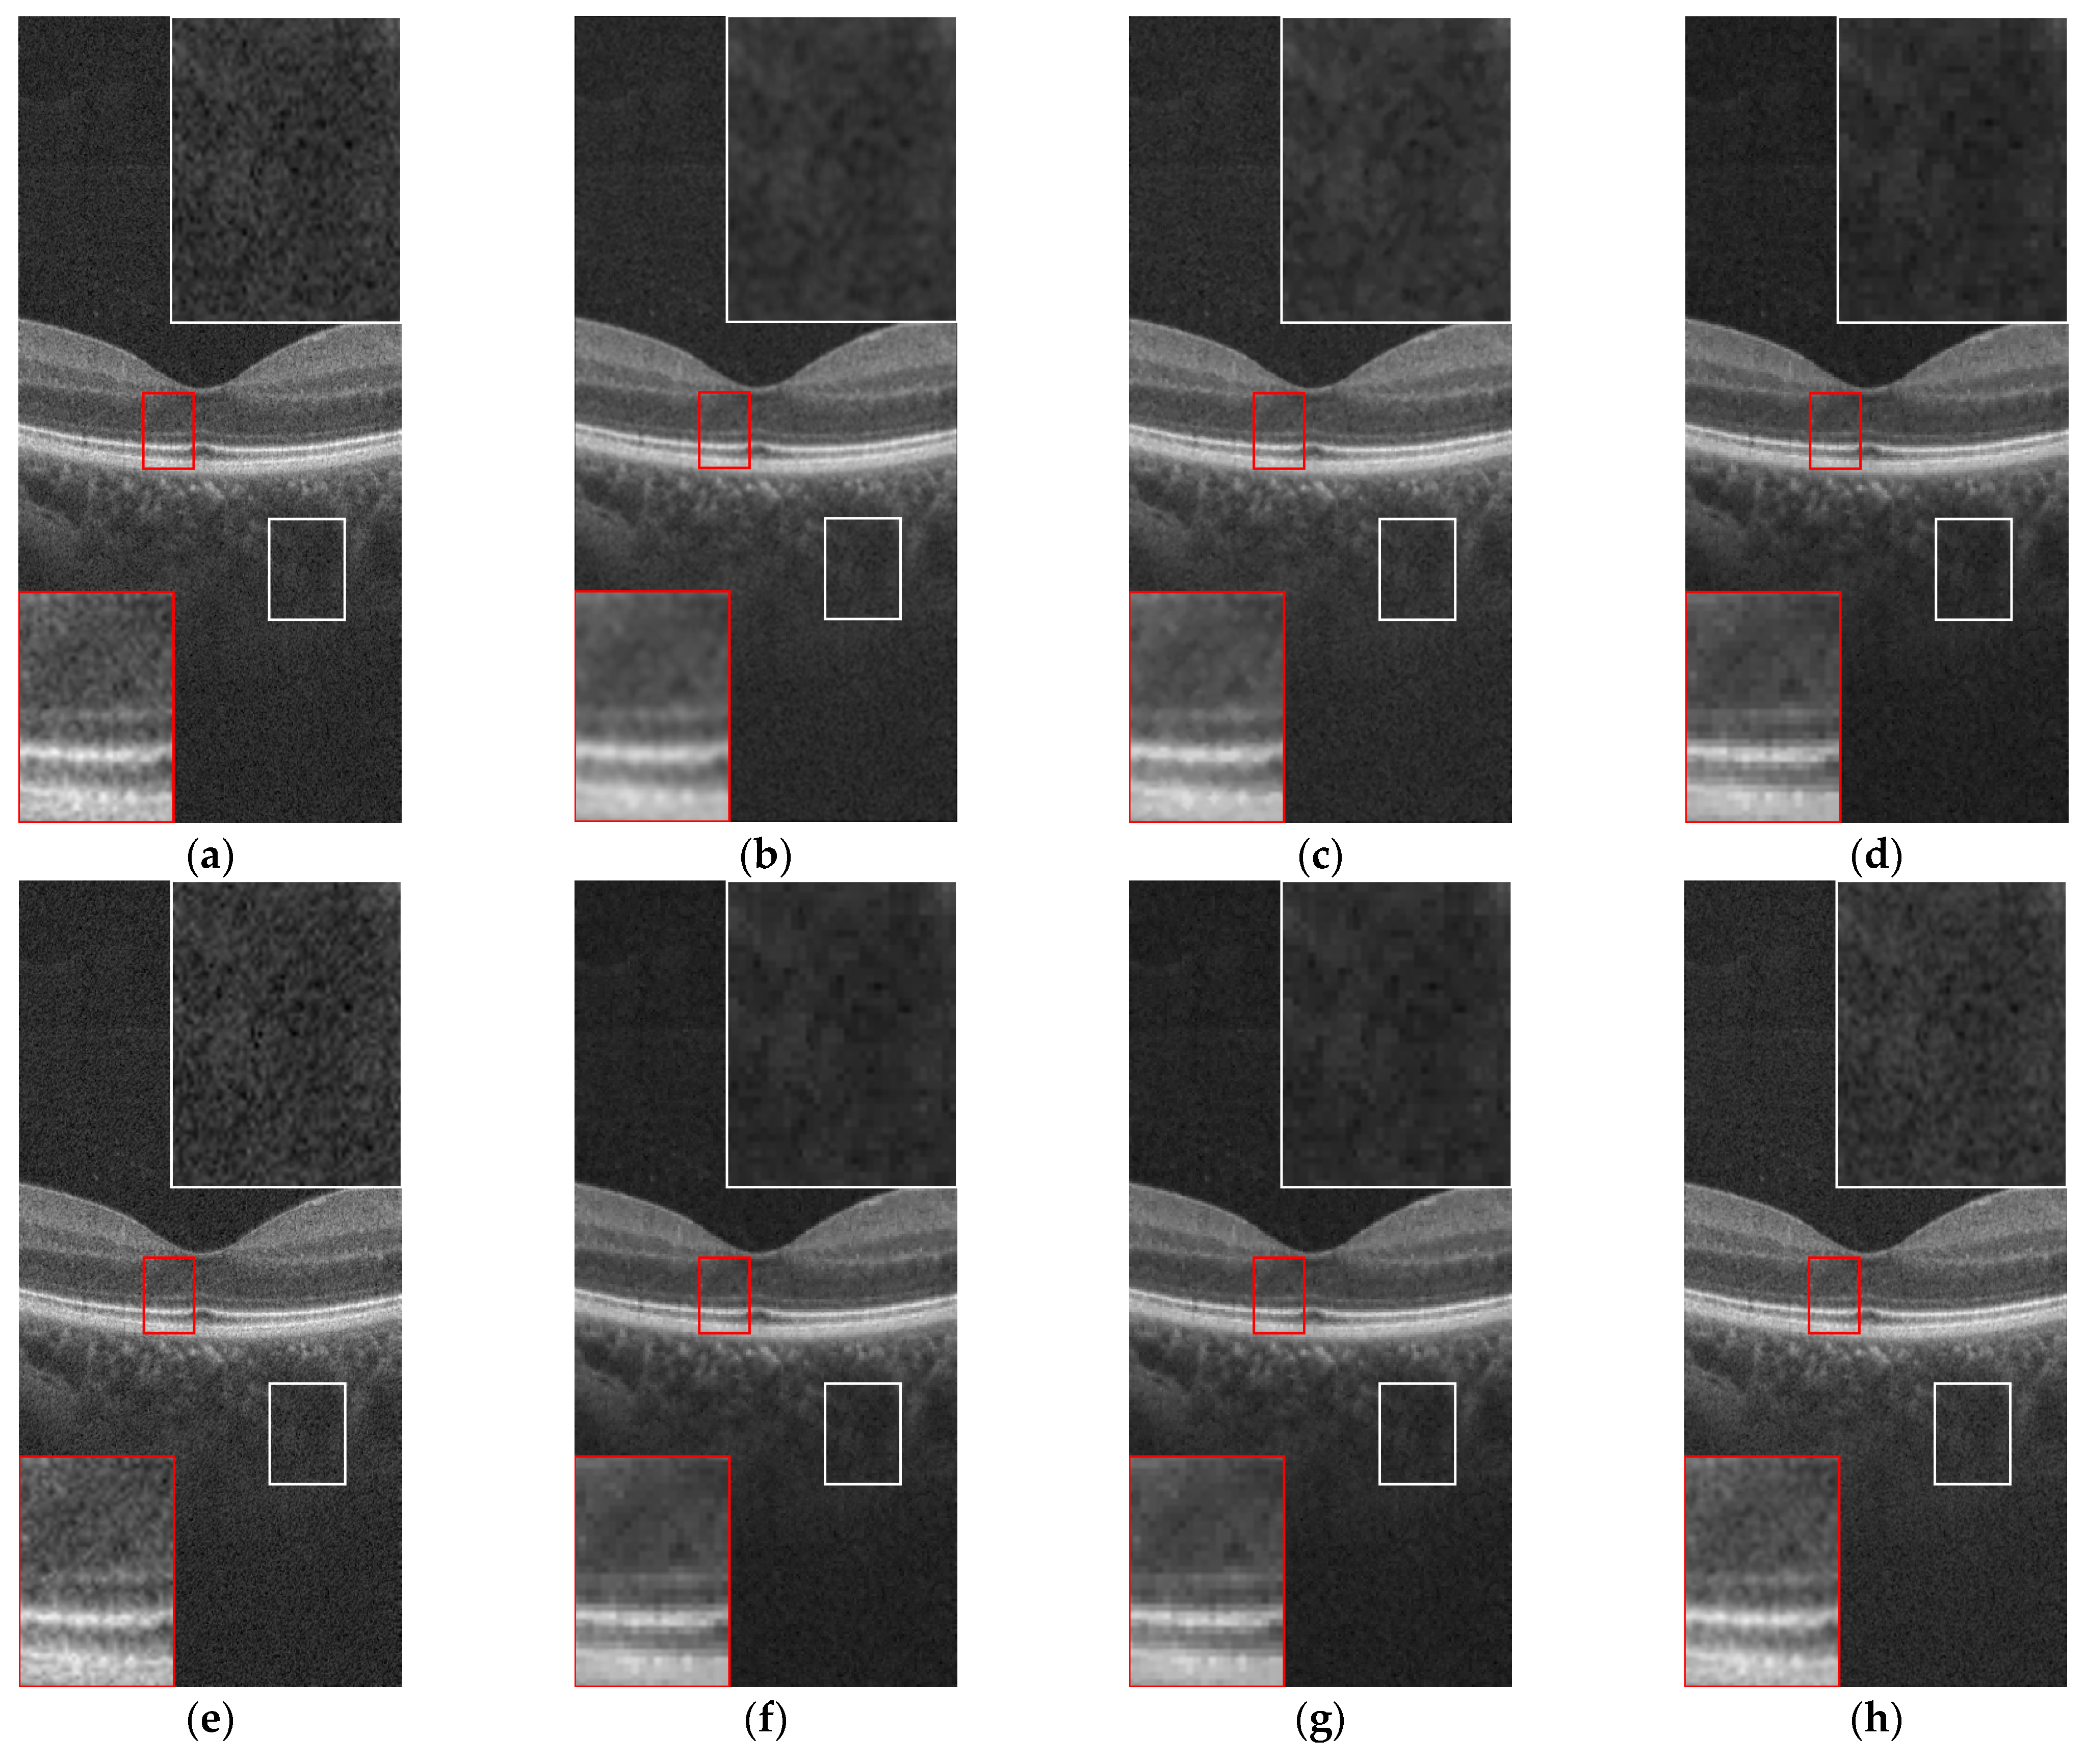

3.2. OCT Image Denoising